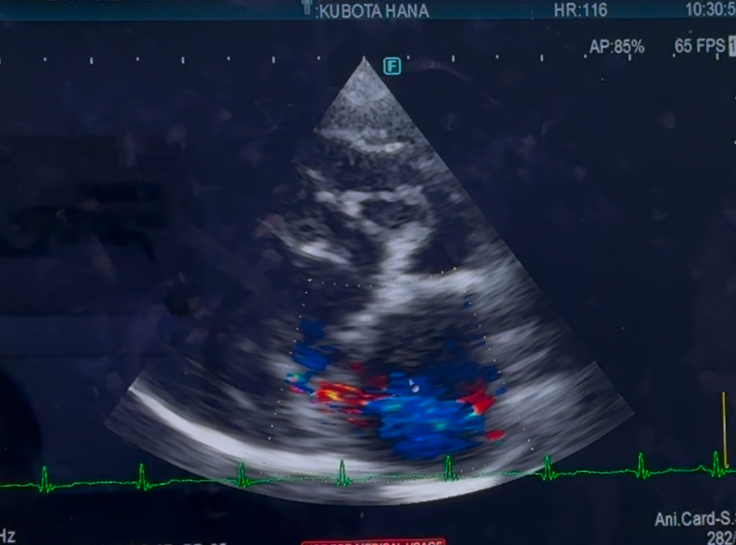

心臓手術後 1年4ヶ月検診でした

心臓手術後検診(1年4ヶ月)でした

手術した、左心の方は

変わらず逆流は、あるものの

悪化はみられず、変わりなしでした

右心の、三尖弁の逆流は

少し、増えているかも…とのことでしたが

多少の、増減はあるものだと言うことと

数値より、症状があるかどうかにより

対処療法を、していくので

今現在は、咳もほとんどなく

症状は、みられないので

経過見となりました…